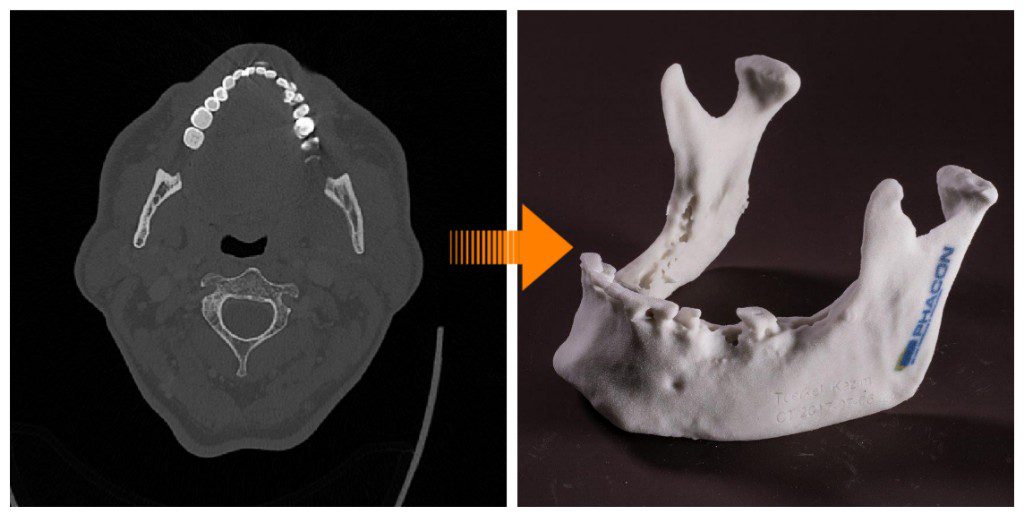

Easy OR preparation with the PHACON Method

Here at PHACON, we base our Artificial Surgical Patients on real Medical Image Data (CT, MR, DVT). Handcrafted from different materials down to the smallest detail. The PHACON Artificial Surgical Patients are individual 3D models based on real-life data including a wide variety of human tissue characteristics (bone, cartilage, muscle, skin and nerves), designed to simulate a wide range of surgeries with interchangeable and compatible PHACON Artificial Surgical Patients of different anatomies. The PHACON Artificial Surgical Patients are also equipped with various trackers that enable precise navigation of surgical instruments to detect injuries. Just like in the OR.